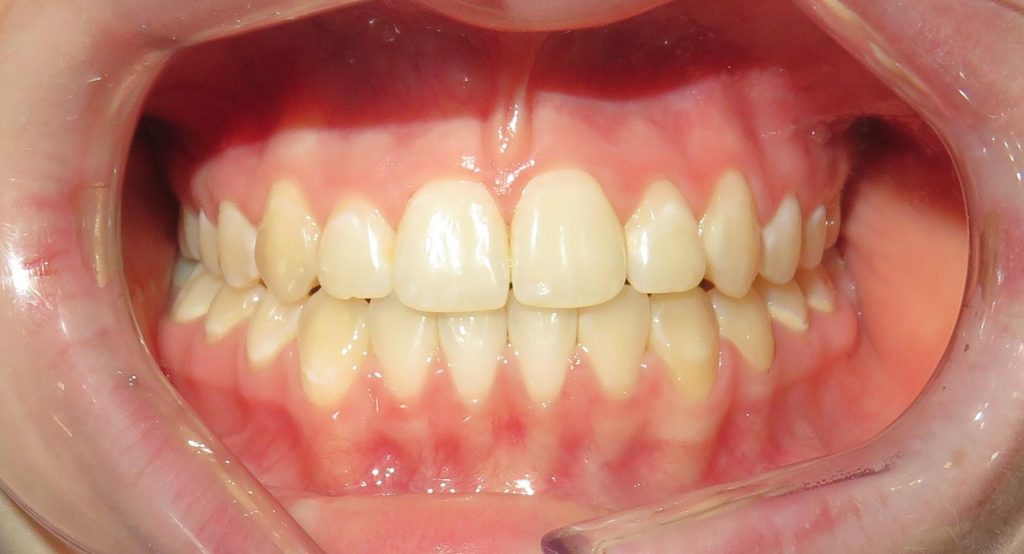

Pod kierownictwem lek. stom. Michała Badowskiego po wnikliwej analizie została przeprowadzona korekta dziąseł i pozbycie się nieestetycznych koron na podbudowie metalowej, eliminując tym samym nawracające stany zapalne dziąseł.

Następnie została wykonana wizualizacja nowego uśmiechu, idealnie dopasowana do twarzy Pacjentki. Po jej akceptacji, przygotowaliśmy komplet koron i licówek pełnoceramicznych na górne i dolne zęby.

Całe leczenie trwało zaledwie 3 miesiące!

Dzięki współpracy lek. stom. Michała Badowskiego i techn. dent. Joanny Gancarz z laboratorium Dentalscan Pacjentka zachwyca pięknym uśmiechem!